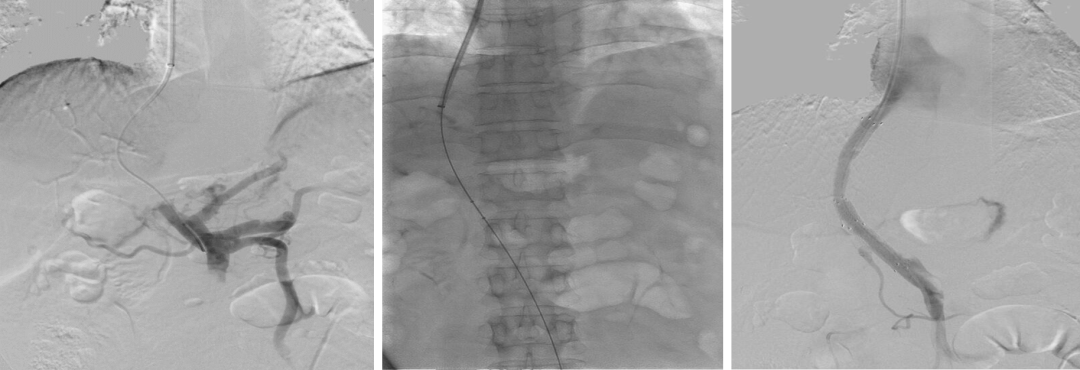

支架与穿刺路径优化

早期:采用裸支架 + 覆膜支架对接,易发生再狭窄;

穿刺策略:初期多选择门静脉右支(操作相对简单),但常导致分流道成角、盖帽,再狭窄率高;后期转向左支穿刺,路径更直,长期通畅率显著提升。

初期TIPS(裸支架—覆膜支架)

初期TIPS(技术的挑战)

门静脉右支穿刺

门静脉左支穿刺